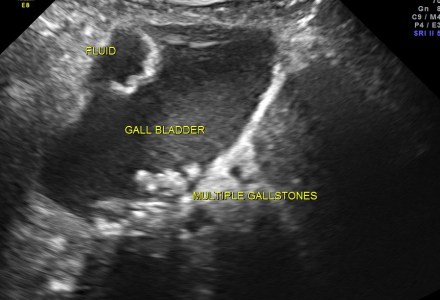

ACUTE CHOLECYSTITIS WITH SUB DIAPHRAGMATIC COLLECTION